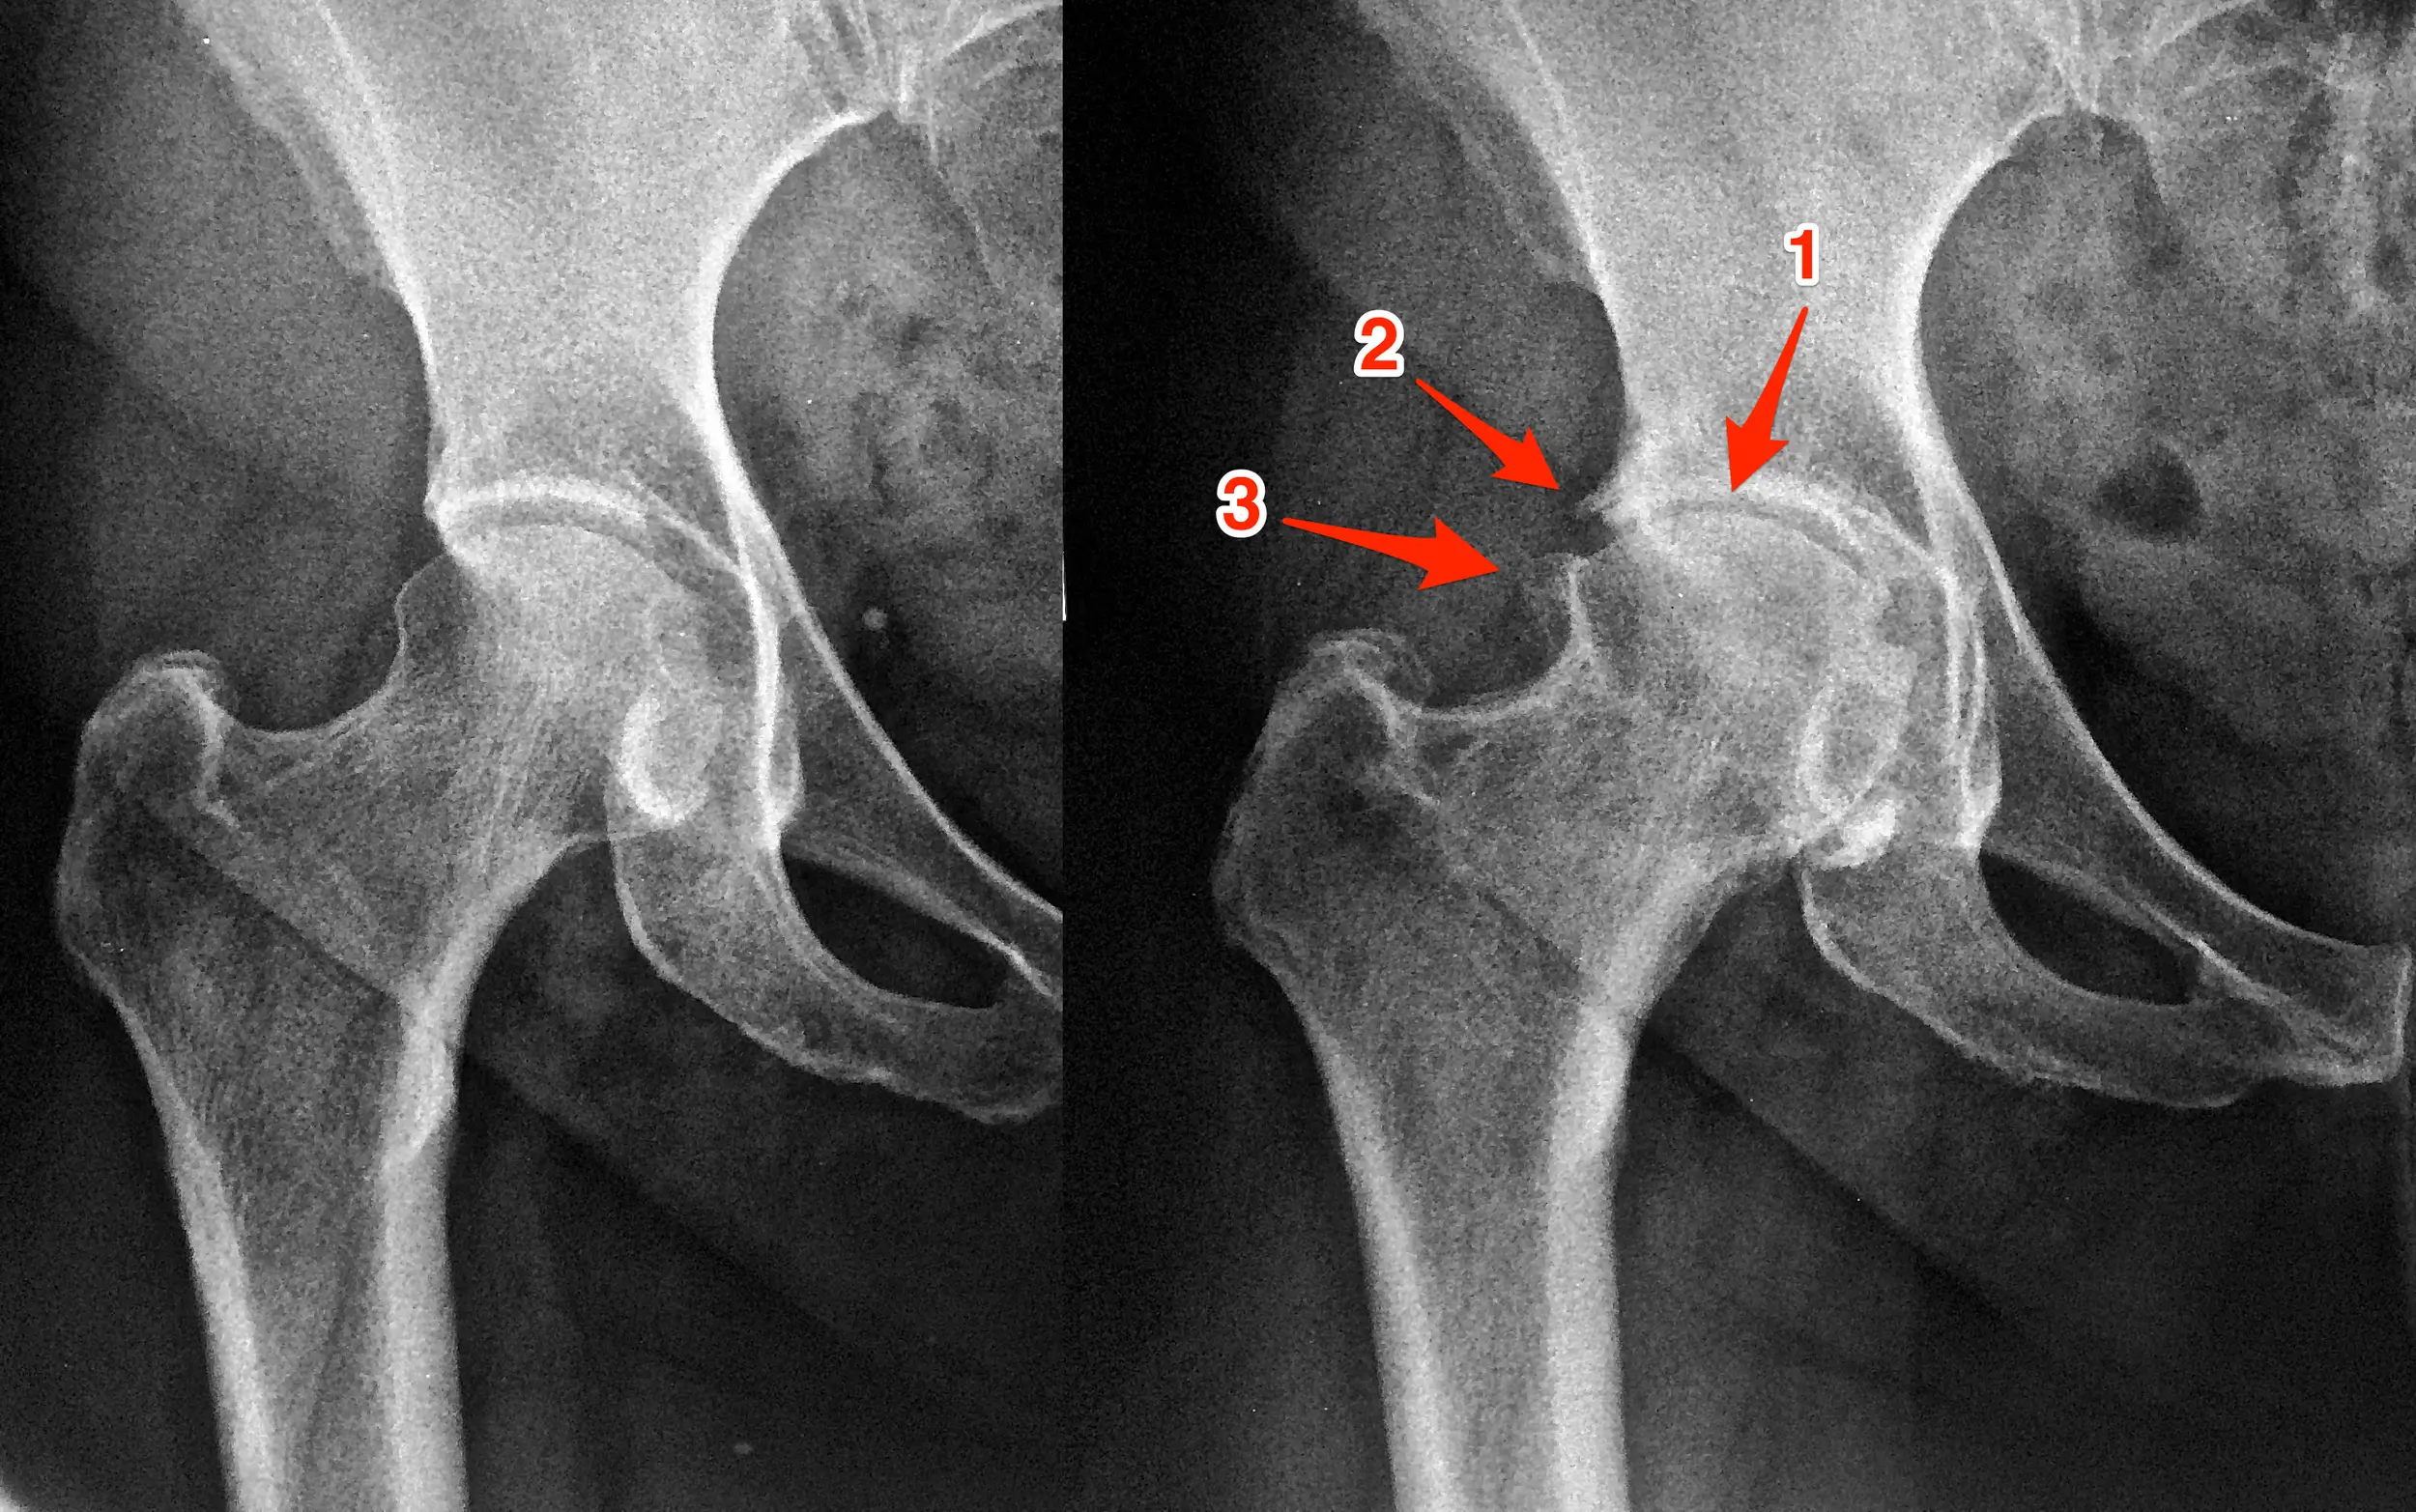

A articulação do quadril é formada pela cabeça do fêmur e pelo acetábulo (parte da bacia), ambos revestidos por cartilagem. Essa cartilagem permite um movimento suave e sem dor. Na artrose, essa cartilagem se deteriora progressivamente, resultando em dor, inflamação e dificuldade para caminhar, sentar ou realizar atividades cotidianas.

O diagnóstico é feito por um ortopedista através de exame físico e exames de imagem, como radiografias, que mostram o estreitamento do espaço articular e a presença de osteófitos (bicos de papagaio).